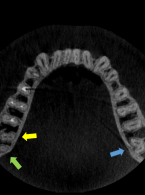

Podczas leczenia endodontycznego zęba 37 (dolny lewy drugi ząb trzonowy żuchwy) u 48-letniego mężczyzny pacjent zasygnalizował ból. Doszło do tego w trakcie wypełniania kanału korzeniowego pastą jodoformową. Ból obejmował lewą stronę twarzy, promieniował do pozostałych zębów lewej strony żuchwy i do okolicy lewego kąta ust. Na zdjęciu zębowym wykonanym bezpośrednio po pojawieniu się bólu zdiagnozowano zacienienie rzutujące się w przebiegu kanału żuchwy. Jakie powinno być postępowanie po przepchnięciu materiału do kanału żuchwy i jak można uniknąć takiego powikłania?